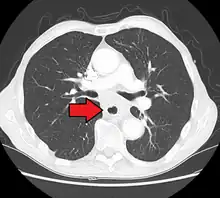

Additional testing is needed to assess how much the cancer has spread (see #Staging, below). Computed tomography (CT) of the chest, abdomen and pelvis can evaluate whether the cancer has spread to adjacent tissues or distant organs (especially liver and lymph nodes). The sensitivity of a CT scan is limited by its ability to detect masses (e.g. enlarged lymph nodes or involved organs) generally larger than 1 cm.[41][42] Positron emission tomography is also used to estimate the extent of the disease and is regarded as more precise than CT alone.[43] Esophageal endoscopic ultrasound can provide staging information regarding the level of tumor invasion, and possible spread to regional lymph nodes.